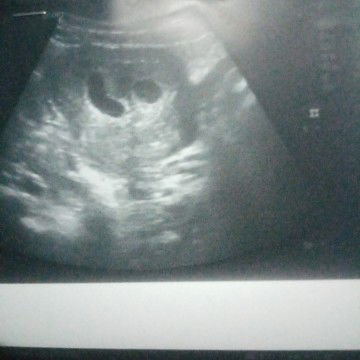

ตั้งครรภ์​แฝด

แบบนี้เค้าเรียกว่าครรภ์​แฝดไหมค่ะ....ไม่เคยมีท้องแฝดค่ะ 6สัปดาห์​ค่ะวันนี้อัลตร้าซาว​3รอบก้อเจอแบบนี้ค่ะหมอเลยบอกอาจตั้งครรภ์​แฝด... หมอเลยนัดตรวจอิกรอบเดือนหน้าค่ะ#สอบถามค่ะ